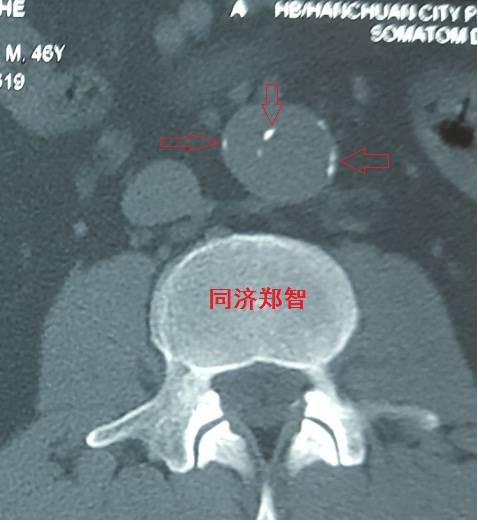

腹主动脉平扫CT提示正常外周一圈的钙化影中有内移的钙化影(红色箭头所示),CTA 证实为腹主动脉夹层